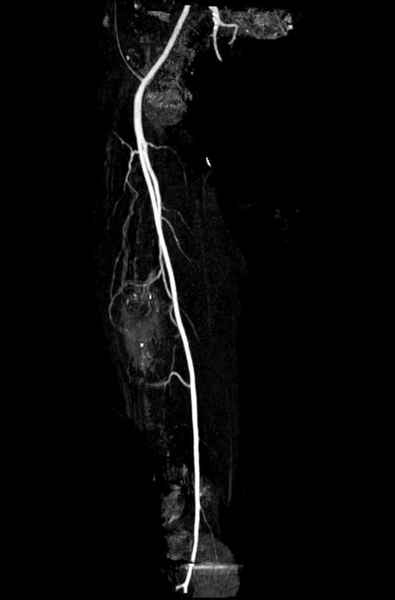

Для предупреждения кровотечения во время рассверливания, за день до операции провели эмболизацию сосудов питающий метастаз. http://radiology.rsnajnls.org/cgi/reprint/150/3/673.pdf (7-11, 12-15-16)

С минимальным рассверливанием и ретроградным методом провели остеосинтез бедра 12 мм гвоздем. (17-20)

Кровопотеря во время операции меньше 100 мл.